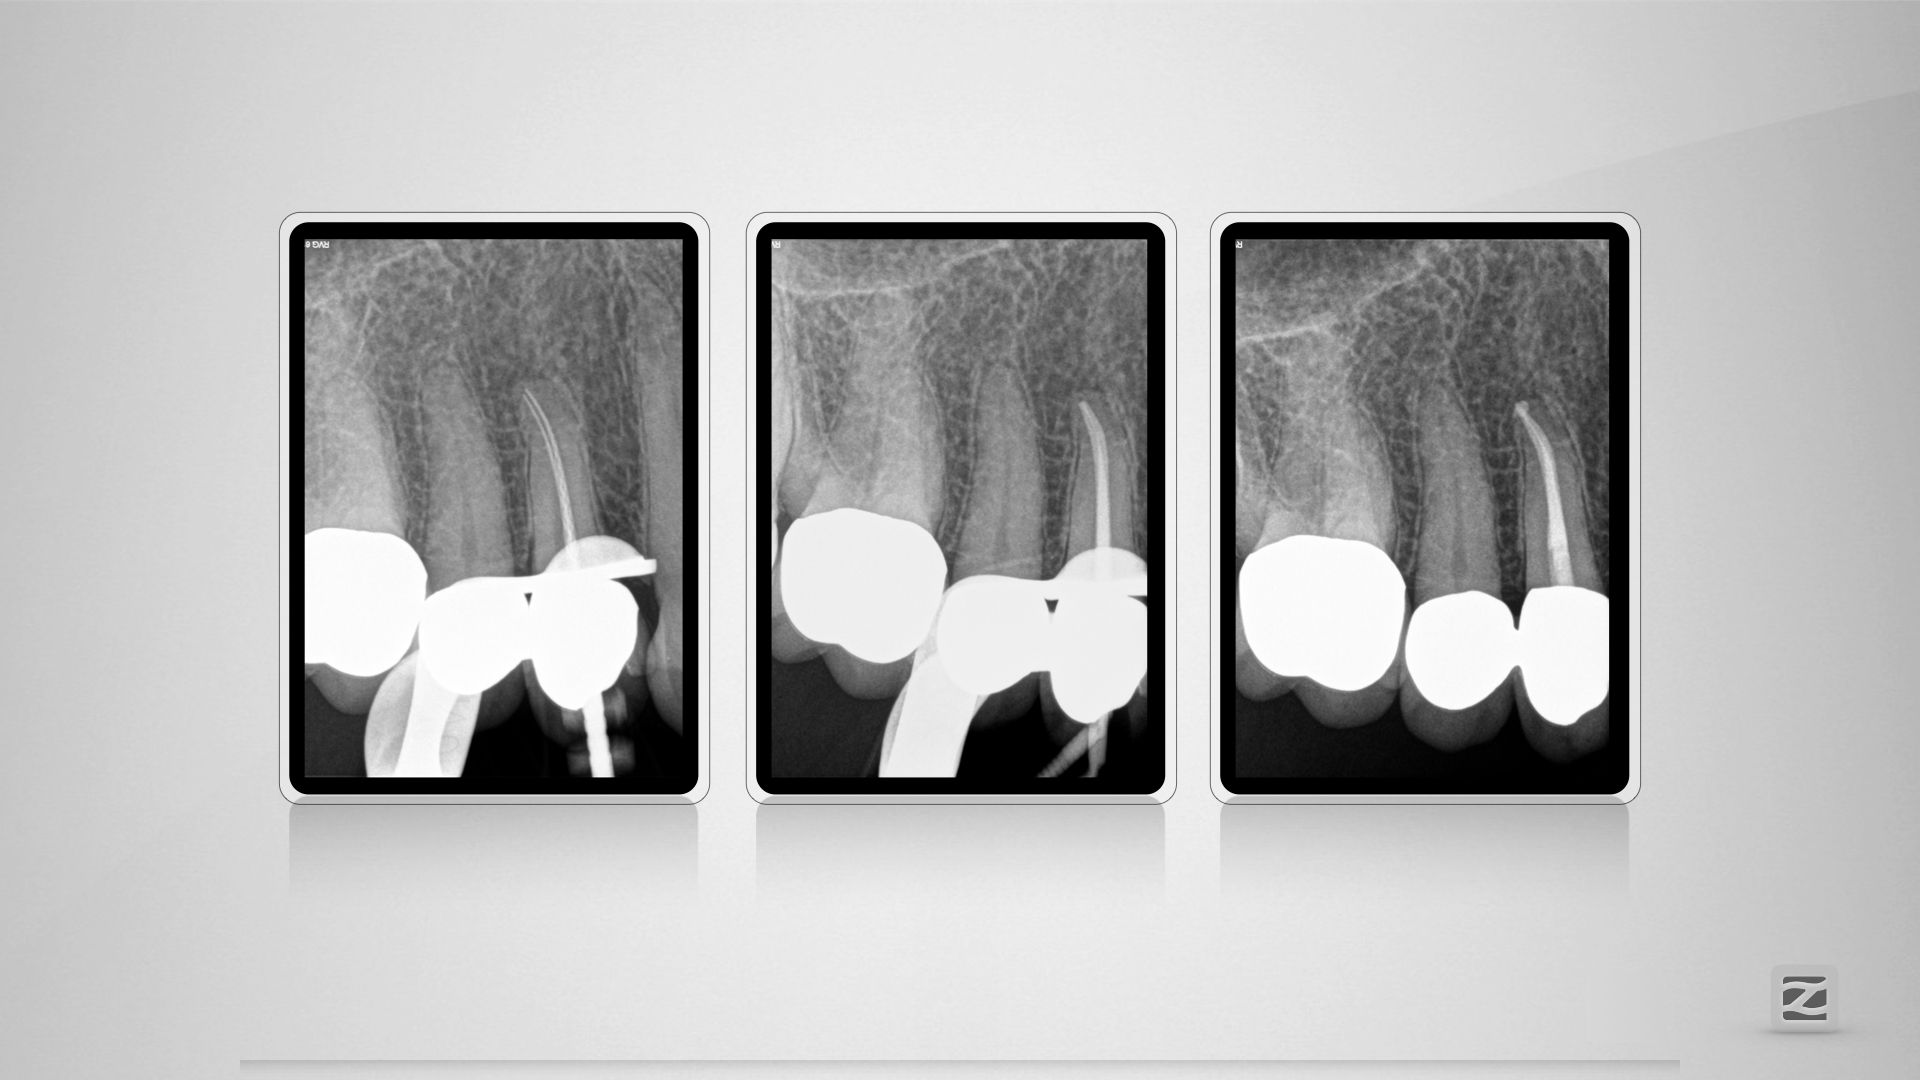

14D.011

H mit kleiner Tücke